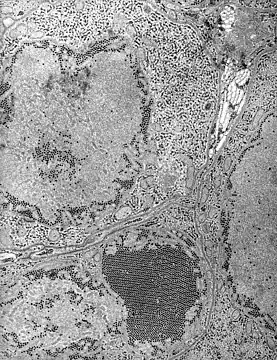

![]() Вірус енцефаліту Сент-Луїс при електронній мікроскопії (чорні цятки) | ||||||||

Збудник — флавівірус групи В родини тогавірусів екологічної групи арбовірусів. Асоційований з енцефалітом. Добре переносить заморожування, висушування і перебування в гліцерині. Швидко руйнується при нагріванні вище 56 °C. Має антигенну спорідненість зі збудниками японського енцефаліту і гарячки Західного Нілу.